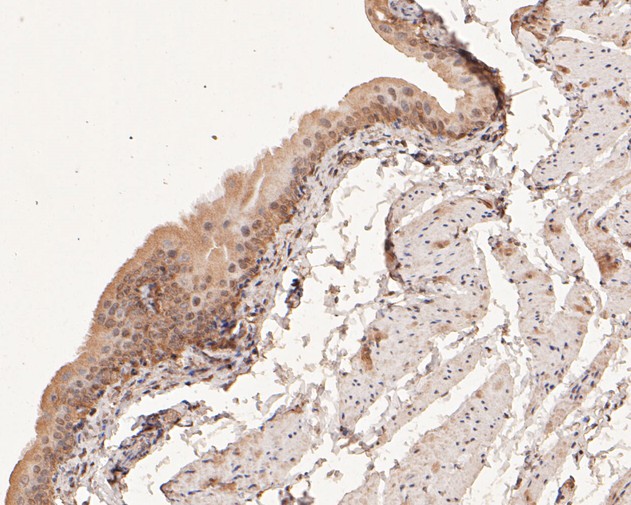

Catalog# EM1902-11

COX2 Mouse Monoclonal Antibody [A3F8]

IHC-P